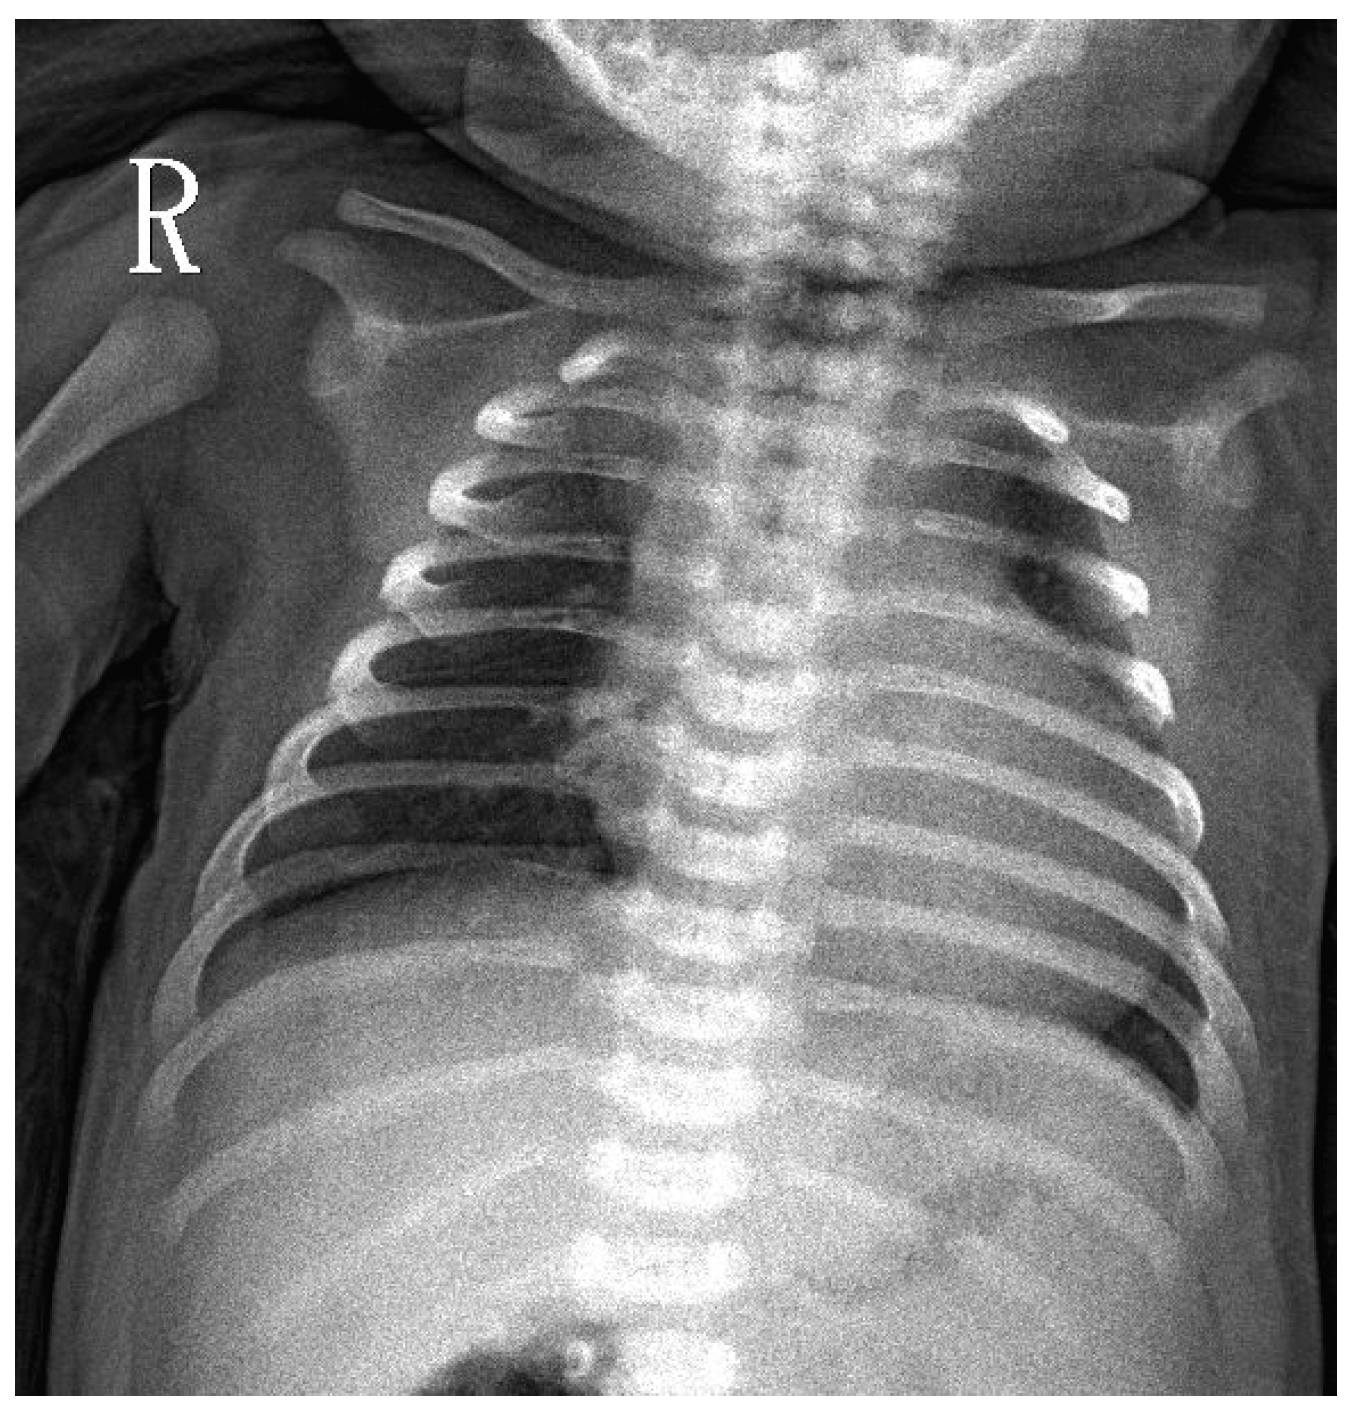

A 7-days-old female newborn was requested to visit our hospital due to an abnormal Pompe disease screening result [13]. She was born at full-term to a G1P1 mother with a birth bodyweight of 4380 gm. The parents denied poor feeding, poor activity, nor weak crying in this baby. NBS included Pompe disease, and other conditions were performed on her third day of life. On Day 4, our NBS laboratory received her sample. On Day 6, a high risk of Pompe disease was reported (GAA activity 0.18 uM/h (critical cutoff < 0.5); ratio 42.87 (critical cutoff acid β-glucosidase (ABG)/GAA ≥ 20) so an urgent visit to our hospital was arranged on Day 7. When we saw her, she had normal muscle power, normal reflex, no macroglossia, but her facial folds decrease slightly. Laboratory examination revealed an elevation of pro-BNP (8738 pg/mL), CK (722 U/L), and alanine aminotransferase (ALT) (112 U/L). A chest X-ray revealed mild cardiomegaly (Figure 1). Echocardiography revealed moderate left ventricle (LV) and right ventricle (RV) hypertrophy, with a LV mass index (LVMI, measured by 2-D method) of 115.7 g/m2 (normal range < 65 g/m2). A whole blood sampling at Day 7 revealed deficient lymphocyte GAA activity (1.33 nmol/g pro/h, normal mean 66.7) and thus confirmed the diagnosis of IOPD. However, she did not have the common CRIM-positive Taiwan Pompe disease p.D645E variant, tested using DNA extracted from the first DBS. Although her CRIM status was unknown, her parents refused prophylactic immune modulation therapy. Western Blot analysis using the white blood cells as the material soon revealed the 110 kDa precursor GAA band (Figure 2), suggesting a CRIM-positive status. She received her first dose of rhGAA (20 mg/kg) at the age of 8 days. Mutation analysis showed heterozygous c.2024_2026del (p.N675del) and c.2040+1G>T variants in trans, compatible with IOPD. There were no CRIM status predictions about these two variants [9].

Figure 1. CXR at D7 in a newborn with a positive Pompe newborn screening result. Mild cardiomegaly was noted.